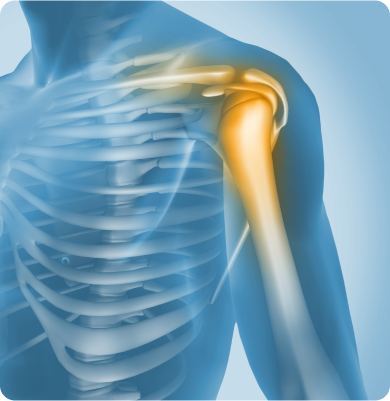

어깨 관절 내 연골이 점진적으로 닳아 없어지는 퇴행성 질환

노화에 따른 관절 연골의 퇴행, 외상, 반복적인 어깨 사용, 과거 탈구나 회전근개 파열 등이 원인이 될 수 있습니다.

어깨 관절이 반복적으로 빠지는 상태가 습관처럼 지속되는 질환

처음 발생한 어깨 탈구 이후 관절이 불안정해지거나 선천적으로 관절이 유연한 경우, 반복적인 외상이나 스포츠 활동으로 인해 발생할 수 있습니다.